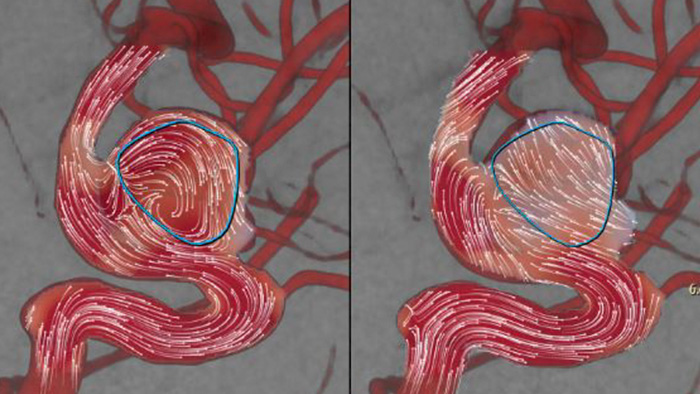

AneurysmFlow is designed to give you relevant information before and after flow diverter deployment. It visualises and quantifies flow changes for greater confidence in procedural effectiveness.